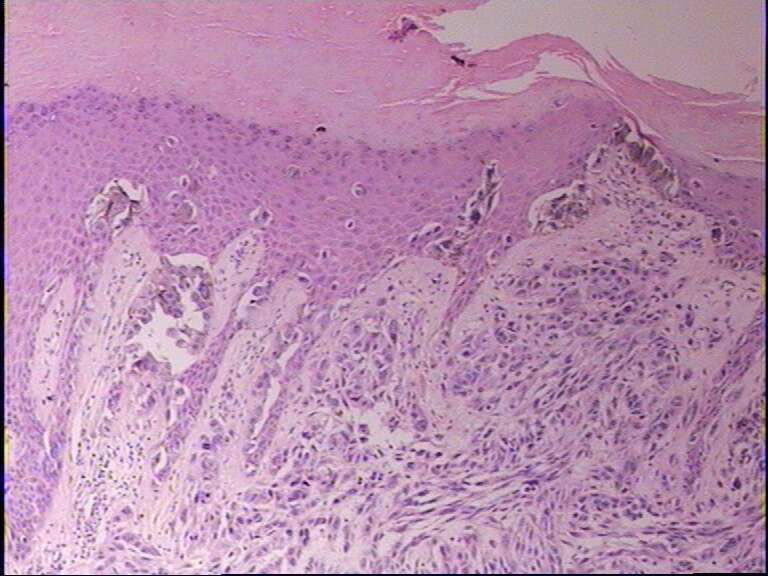

示指末端,指甲下肿物,指甲破坏,黑色面积1*0.7

有亲表皮·现象,细胞形态有异形性,支持恶性黑色素瘤。

1、4图似乎有黑色素细胞对表皮的浸润,支持恶黑

上侵表皮,考虑恶黑。

恶黑和鳞状细胞癌都要考虑